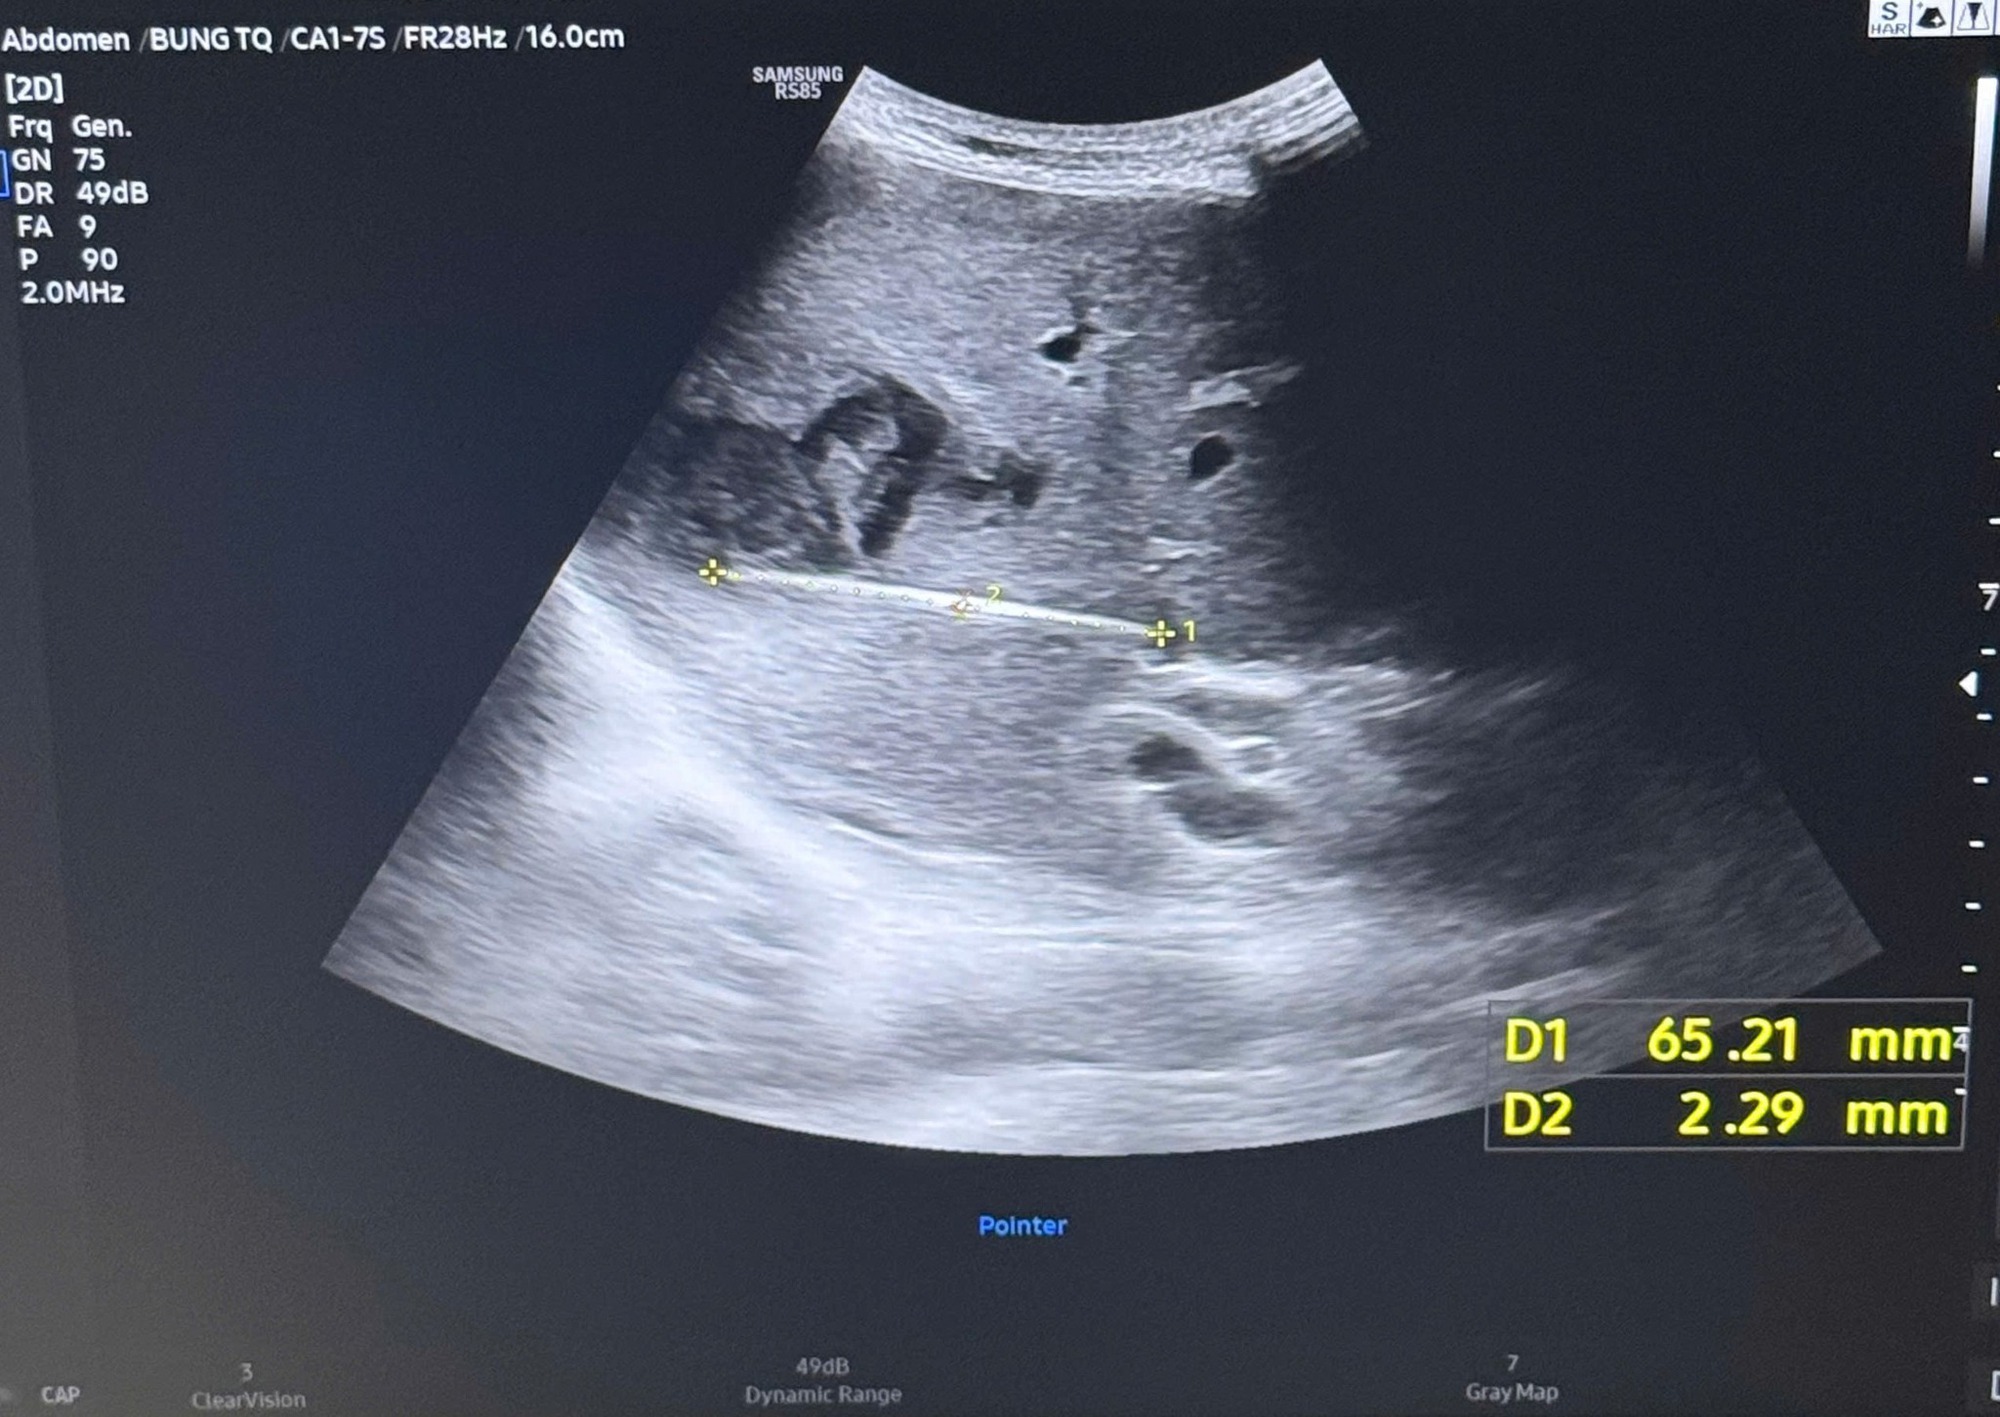

Cây tăm được bác sĩ gắp ra (bên trái) và hình ảnh cây tăm qua siêu âm (bên phải)

Khi tiến hành siêu âm chi tiết hơn, ê-kíp điều trị phát hiện một dị vật cản quang xuyên trong nhu mô gan, dài khoảng 6–7cm. Kết quả chụp cắt lớp vi tính (CT scan) ổ bụng sau đó xác định có một dị vật dạng que dài nằm hoàn toàn trong gan, kèm theo ổ áp xe sâu.